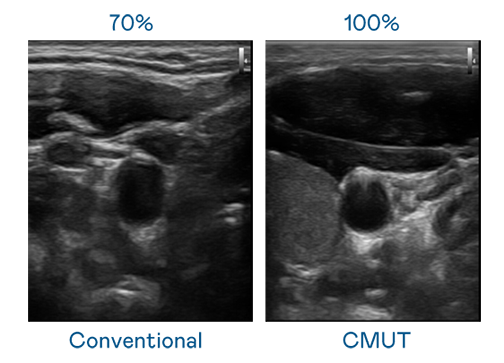

CMUT 技术是一种用电容式微机电元件来产生超音波讯号的技术。与传统 PZT 压电式技术相比,CMUT 频宽增加 30%,更宽频的超音波讯号让影像解析度大幅提升,是实现高影像品质医疗超音波扫描、促进精准医疗发展的关键技术。

超音波影像的解析度高低,首先取决于探头能发出的讯号频宽。非凡游戏 CMUT 可提供高清晰的超音波讯号,提供高频宽、高灵敏度、影像纹理细节更高的超音波影像,协助医护人员缩短影像判读时间及利用精准的医疗影像进行诊断。